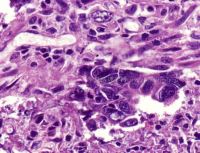

结合临床内镜下黏膜切除术(EMR)和内镜黏膜下剥离术(ESD)进行消化道早期癌的诊断;开展免疫组化进行结直肠癌的微卫星不稳定性(MSI)检测,为结直肠癌患者的预后和化疗药物的选择提供参考;开展结直肠癌KRAS基因突变检测,为患者基因靶向治疗提供依据。